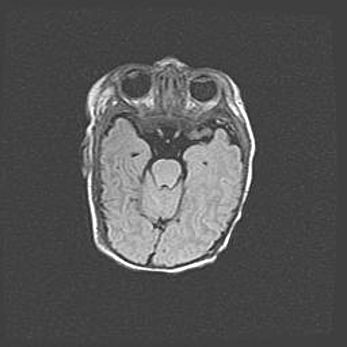

Неполная лизэнцефалия (пахигирия). Открытая гидроцефалия.

Возраст: 17 дней

Вес: 3110 г

Пол: мужской

Окружность головы: 33,5 см

Срок гестации: 35-36 недель

Лизэнцефалия—недоразвитие корковой пластинки и мозговых извилин в результате нарушения миграции нейронов коры. Поверхность мозговых полушарий гладкая. Микроскопически выявляется отсутствие нормальных слоев коры и скопление групп нейронов в подкорковом белом веществе.

Пахигирия—уменьшение числа вторичных извилин. В пораженном полушарии нервные клетки образуют толстый недифференцированный слой с неправильно расположенными нервными волокнами и группами гетеротопных клеток. Нервные клетки незрелые. Белое вещество истончено. При этом нередко аномально развит корково-спинномозговой путь.